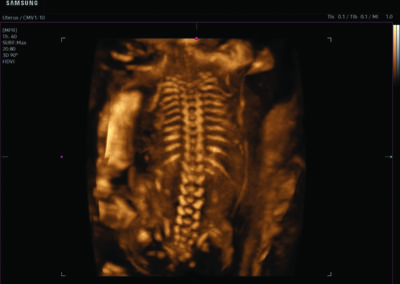

Comprehensive, advanced and expert MFM care for high-risk pregnancies

- Neural tube defects

- Fetal anomalies